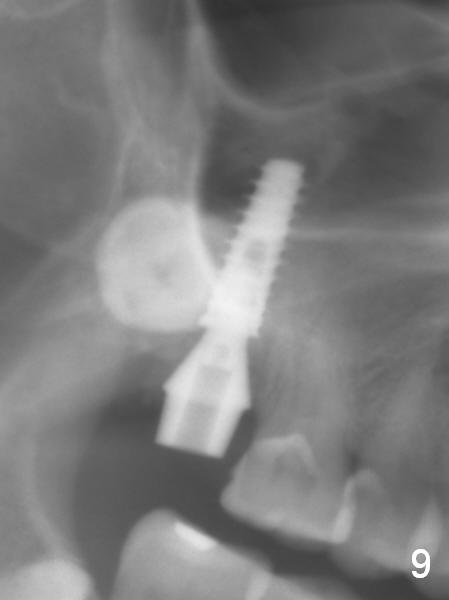

Extraction confirms crack tooth at #2 (Fig.1 (mesial view) <). The buccal (Fig.2 (illustration) B) socket is larger than the palatal (P) one, while the septum (S) is small. Osteotomy is initiated on the buccal slope of the septum (Fig.3 red arrow), followed by Magic osteotomes (Fig.4-7). As the diameter of the osteotomes increases, so does the depth with sinus lift (Fig.5 arrow). The largest osteotome is 4.8 mm. When a 5x13 mm implant is placed, it has low torque (Fig.8,9). The implant resists lateral movement, but keeps turning. When a largest pair abutment with the longest cuff is placed (6.5x4(4) mm to hold an immediate provisional in place), it seems to turn with the underlying implant together for a half turn. Since the provisional is engaged into the distal undercut of the tooth #3 (while the acrylic is setting), it may increase the implant stability. Anyway, overprep in this case leads to low primary stability. For immediate implant, underprep is a must. For this case, the last osteotome should have been 4.3 mm (.7 mm (one or two size(s)) smaller than the implant). When the implant is found to have low torque value, remove it, place bone graft in the osteotomy site and surrounding socket for sinus lift as well and place the implant again. The primary stability should have been increased. Preferably, a larger implant should be used (5.5 mm). Fortunately there is nasal hemorrhage postop. Reexamination of the extracted tooth after being soaked in bleach for 2 days confirms that the mesial (Fig.10 M) and distal (Fig.11 D,12 <) crack lines extend intrapulpally (^).